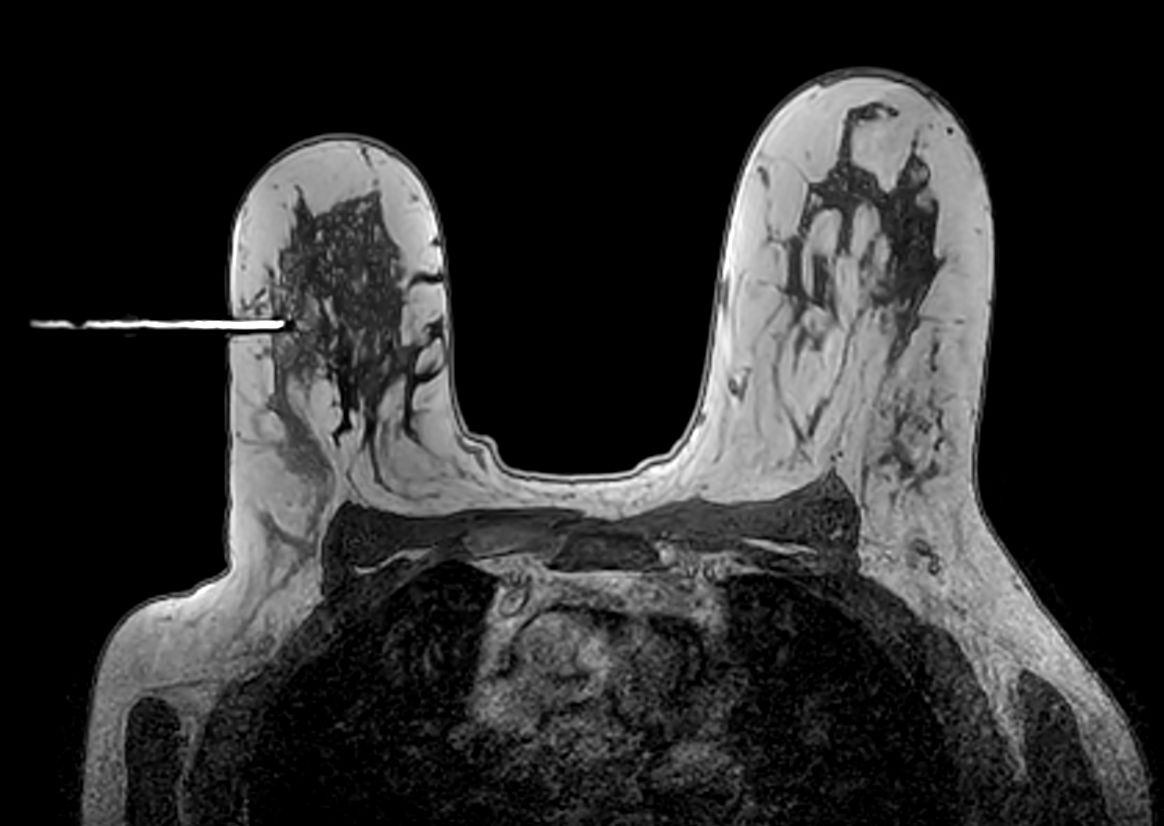

Axial 3D T1w FFE - Confirmation Fudicial marker positioning too high